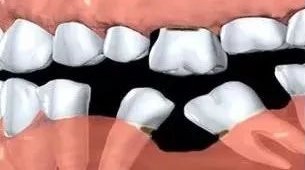

3、缺牙后没及时修复造成两侧牙倾斜,造成两侧牙齿之间的间隙。

3、牙齿缺失后应尽早进行修复治疗,在两侧牙齿向缺隙倾斜后将会增加治疗难度,需先进行正畸治疗将倾斜的牙齿直立消灭间隙后再进行修复治疗。